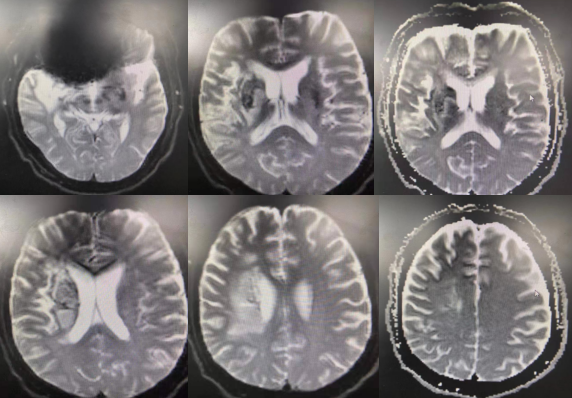

头颅MRI:

(患者有金属义齿,核磁仅弥散相较清楚)未见脑出血征象,右侧基底节区、颞叶、侧脑室体旁多发点片状异常信号影。